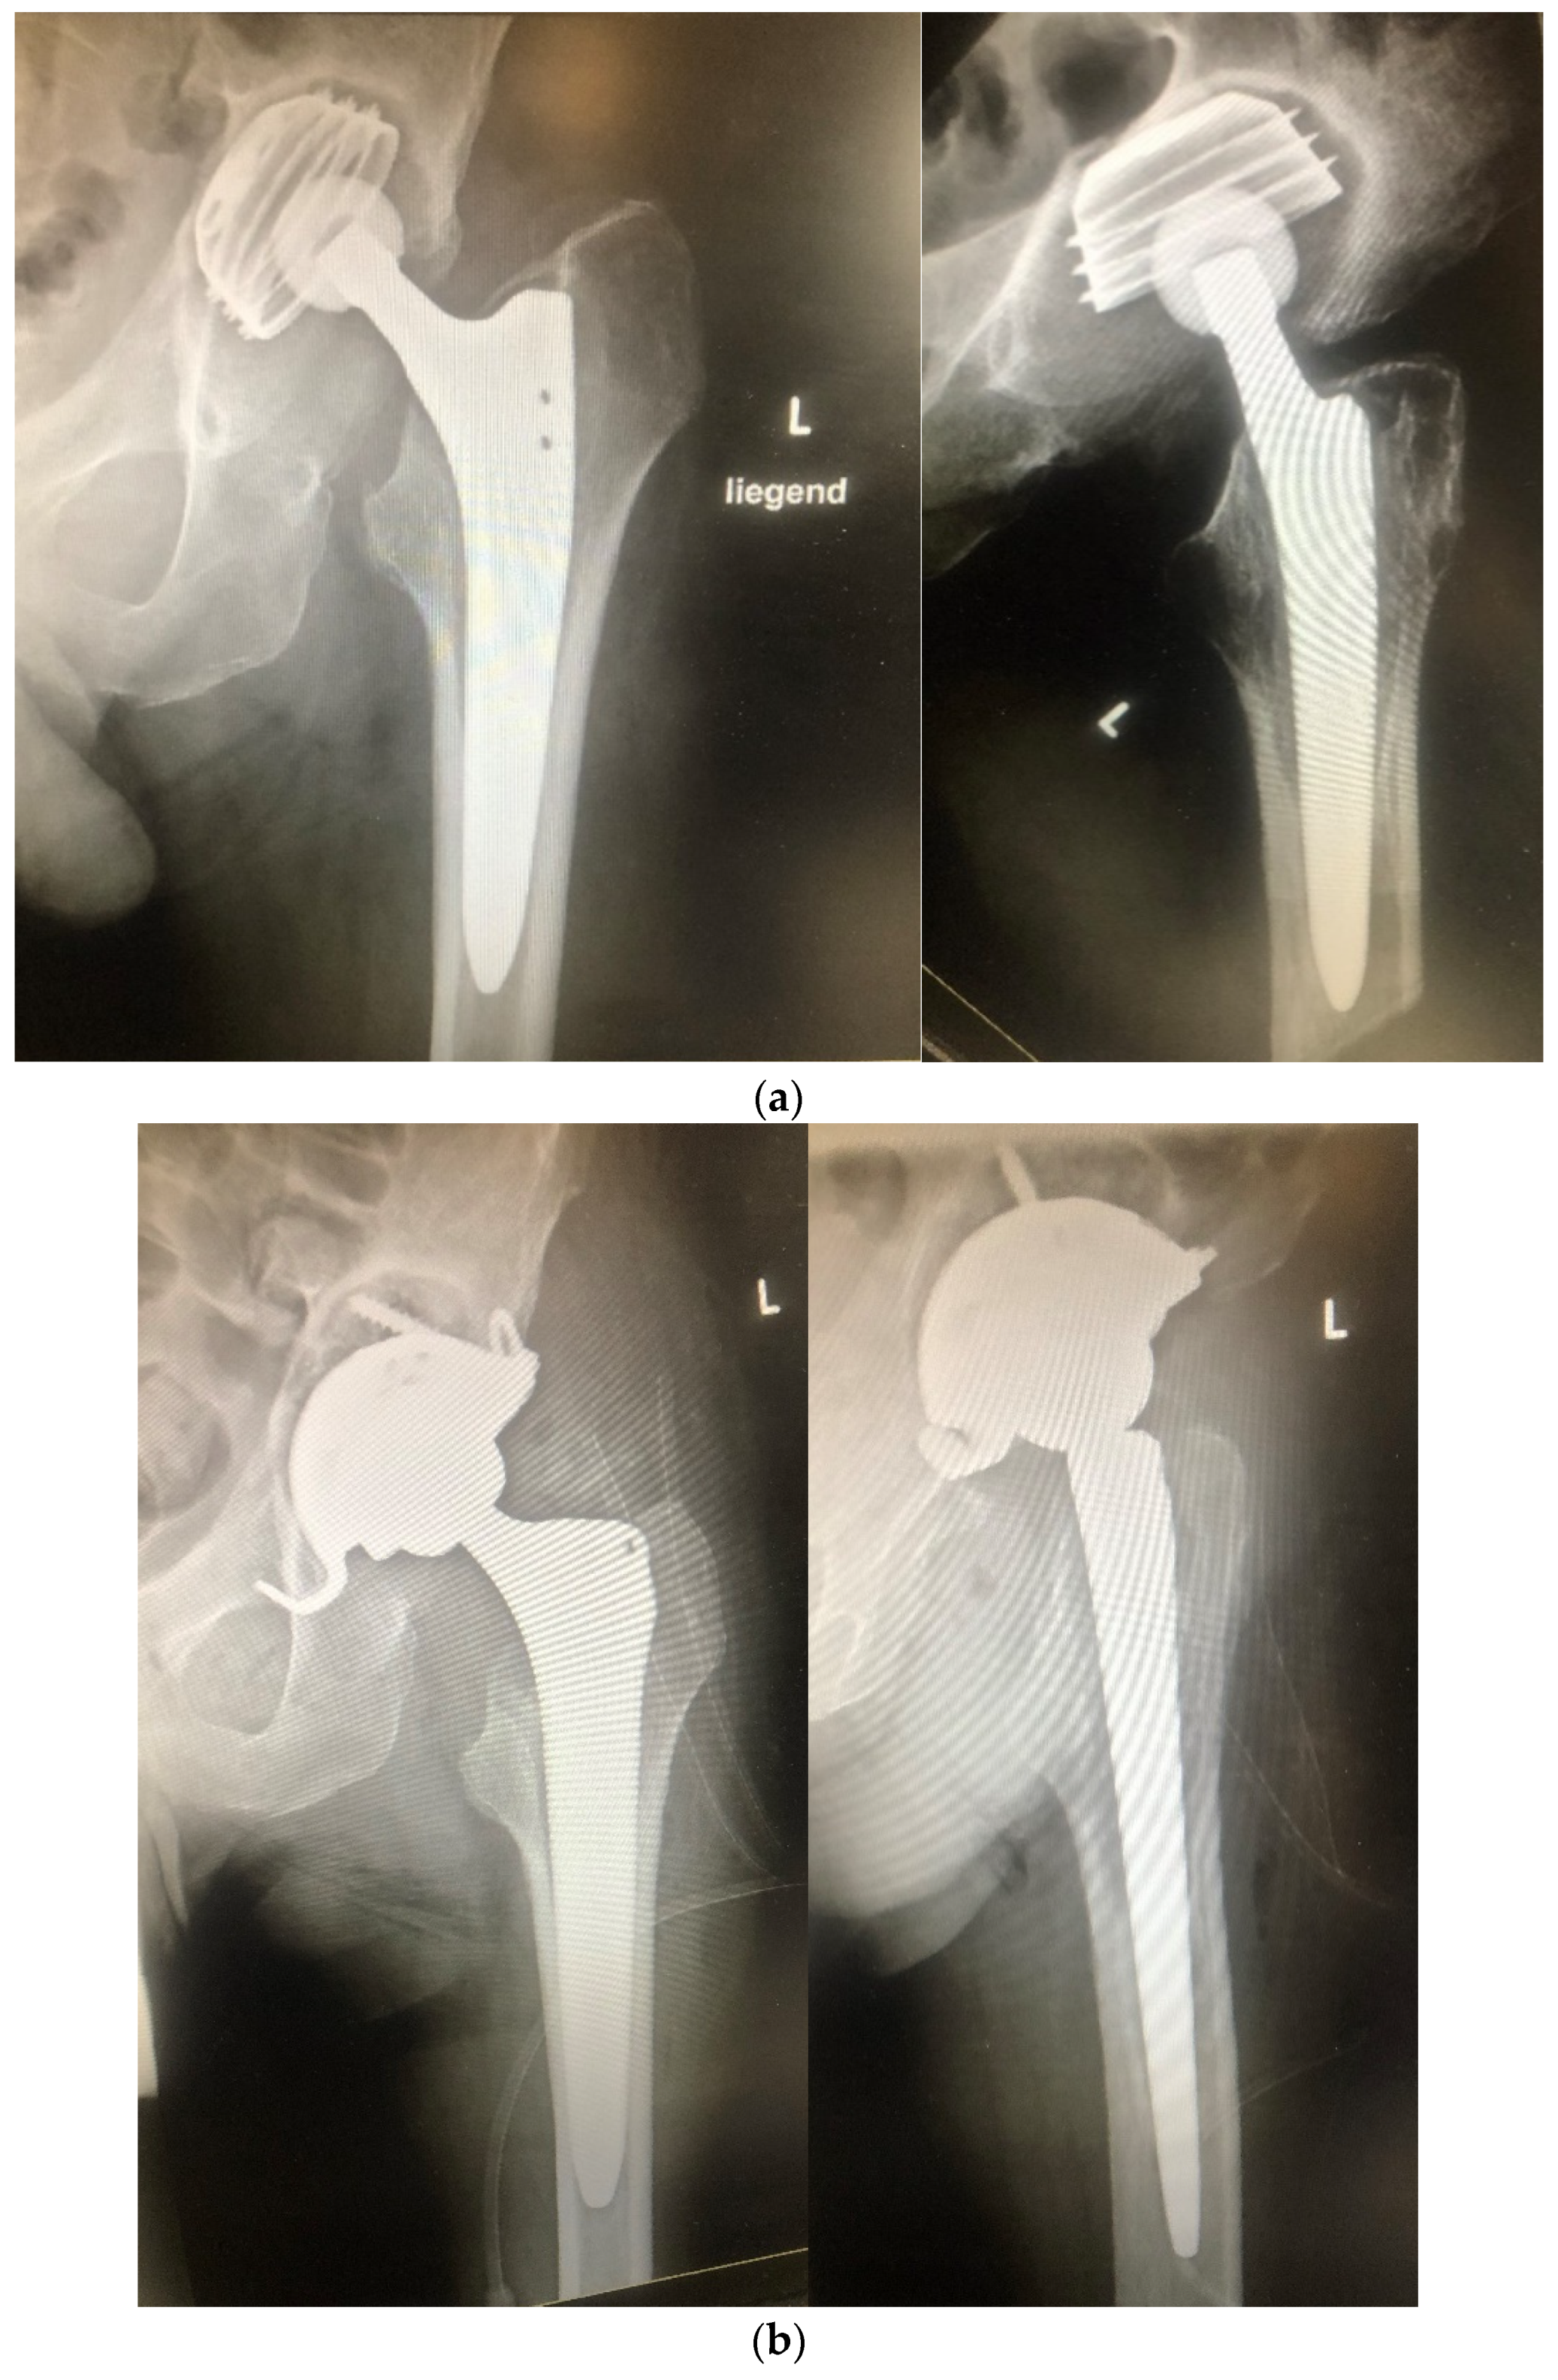

| Hip Joint | 38 (54.3%) |

| Cementless prosthesis implantation | 49 (70%) |